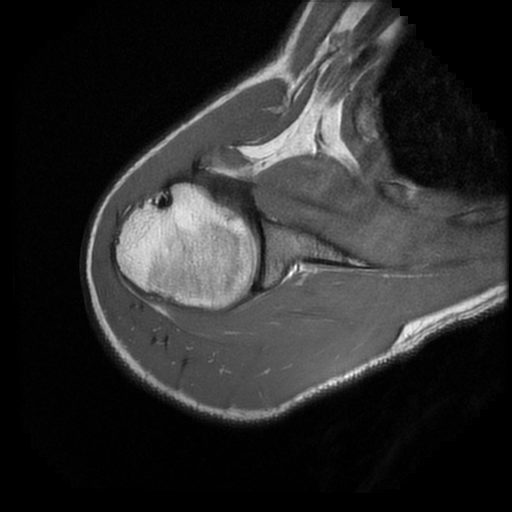

TECNICA EMPLEADA

Se coloca al paciente en decúbito supino, utilizando bobina dedicada de 8 canales, obteniendo imágenes en planos axial, sagital y coronal, secuencias, Spin Echo, Eco de Gradiente, potenciadas a Densidad de Protones, con pulsos de saturación de grasa.

HALLAZGOS IMAGENOLOGICOS

Lesión post traumática de Hill Sachs a nivel de la cabeza humeral, tendinosis aguda del supra espinoso.

La lesión de Hill-Sachs es un defecto de impactación en la región posterosuperolateral de la cabeza humeral, secundario a luxación o subluxación anterior del hombro. Se produce cuando la cabeza humeral, desplazada anteroinferiormente, colisiona y se “muerde” contra el borde anteroinferior de la glenoides.